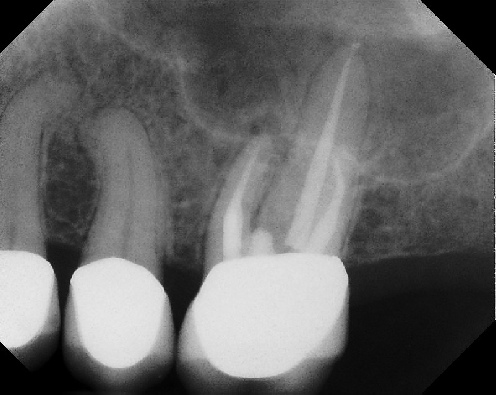

COMPLICATED ANATOMY LARGE LESIONS CALCIFIED CANALS PERFORATION / RESORPTION SEPARATED INSTRUMENTS SURGICAL CASES RETREATMENT / pOST REMOVAL OPEN APICES ACCESS THRU CROWNS Root Canal Case Portfolio